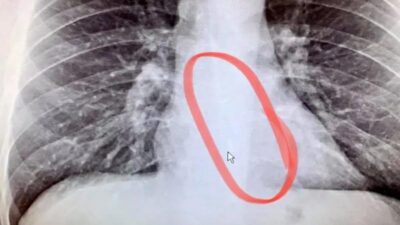

‘Bırakın bir yere gitmeyi, yemek yerken dahi nefes nefese kaldığım oldu’

Boğaz kuruluğu nedeniyle doktora başvurdu, içinden kulaklık çıktı!